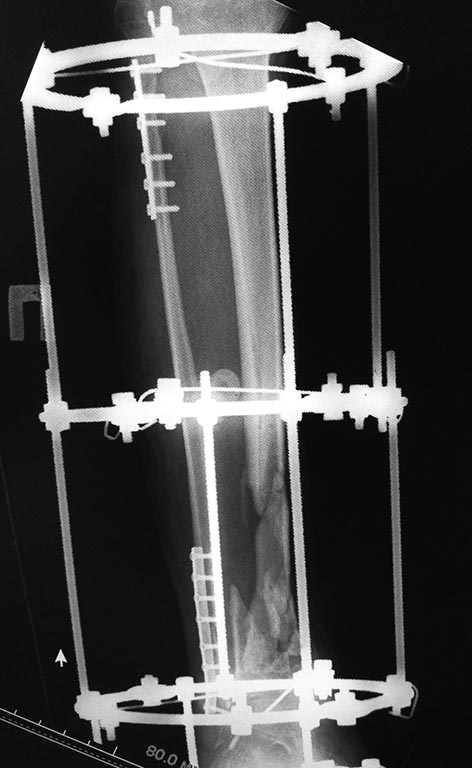

Что касаемо голени, перелом был закрытый. Выполнена открытая адаптация отломков б/берцовой кости, комбинированный остеосинтез костей голени. Рана зажила первично.

Представляю вам снимки первичные при поступлении и голень в аппарате на сегодняшний день. Тактическое предложение следующее:

Спицевой аппарат Илизарова уж больно "хлипенький". Скорее всего, нет должной стабильности. Нет стабильности - нет восстановления кровотока в промежуточных фрагментах. Возникает вопрос о их жизнеспособности (отсутствует периостальная реакция). Нужно начать с аппарата внешней фиксации!!!